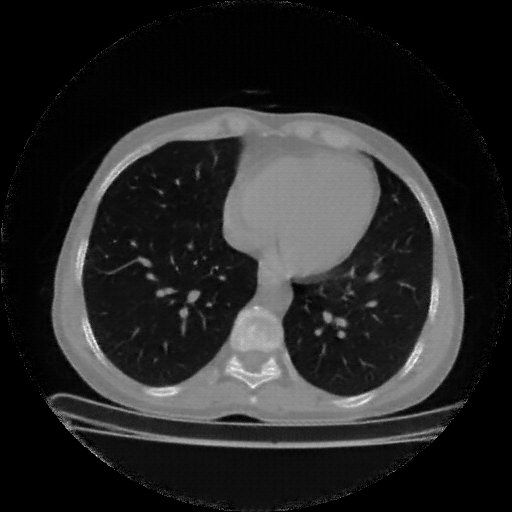

Original VENOUS CT scan

Full window (WL 1023.5, WW 4095 β†’ Low βˆ’1024, High +3071)

Lung window (WL -600, WW 1500 β†’ Low βˆ’1350, High +150)

Mediastinum window (WL 40, WW 400 β†’ Low βˆ’160, High +240)